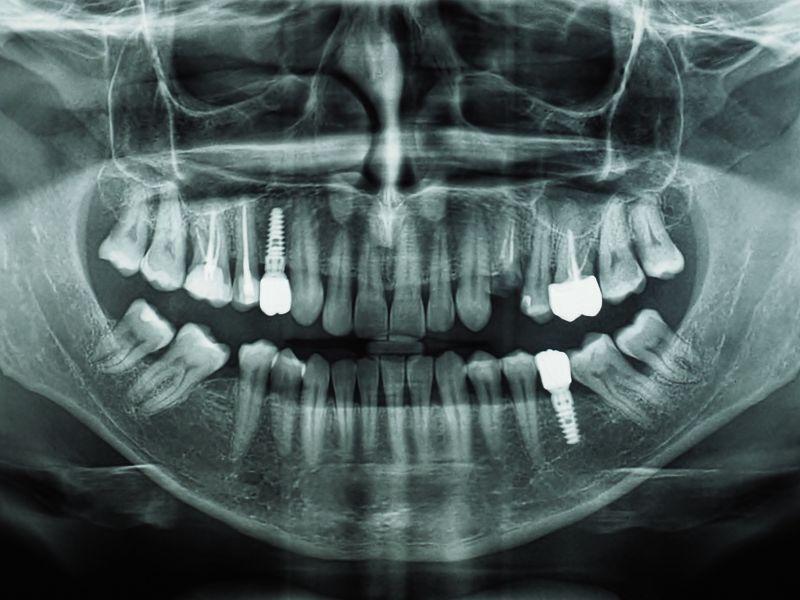

W dziedzinie stomatologii pantomogram jest nieocenionym narzędziem, które umożliwia szybką i kompleksową ocenę stanu uzębienia, co udowadnia praktyka xray.pl. To zdjęcie rentgenowskie jest wykorzystywane do identyfikacji różnych problemów stomatologicznych, takich jak próchnica, choroby przyzębia, niewyrżnięte zęby mądrości, a także do oceny stanu implantów zębowych. Umożliwia ono wykrycie problemów, które mogłyby pozostać niewidoczne podczas rutynowego badania stomatologicznego.

Pantomogram jest niezastąpiony przy planowaniu bardziej złożonych procedur, takich jak wyrywanie zębów czy wszczepianie implantów. Dzięki niemu stomatolog może dokładnie zaplanować zabieg, minimalizując ryzyko komplikacji i zapewniając pacjentowi jak najlepsze efekty leczenia. Wszystko to sprawia, że pantomogram jest nie tylko przydatny, ale wręcz niezbędny w nowoczesnej stomatologii.

Pantomogram odgrywa niezastąpioną rolę w planowaniu leczenia stomatologicznego. Na podstawie obrazu możliwe jest dokładne zaplanowanie zabiegów, ocena ryzyka oraz przewidywanie potencjalnych komplikacji. To zdjęcie jest fundamentem skutecznego planowania leczenia, zarówno w przypadku standardowych procedur, jak i tych bardziej skomplikowanych.

Współczesna diagnostyka stomatologiczna nie może obejść się bez pantomogramu. Jego rola w ocenie stanu zdrowia jamy ustnej jest nieoceniona, a dzięki ciągłemu rozwojowi technologii, badanie to staje się coraz bardziej dostępne i bezpieczne dla pacjentów. Wykorzystanie pantomogramu w diagnostyce i planowaniu leczenia zwiększa skuteczność terapii i pomaga w utrzymaniu zdrowia jamy ustnej na najwyższym poziomie.